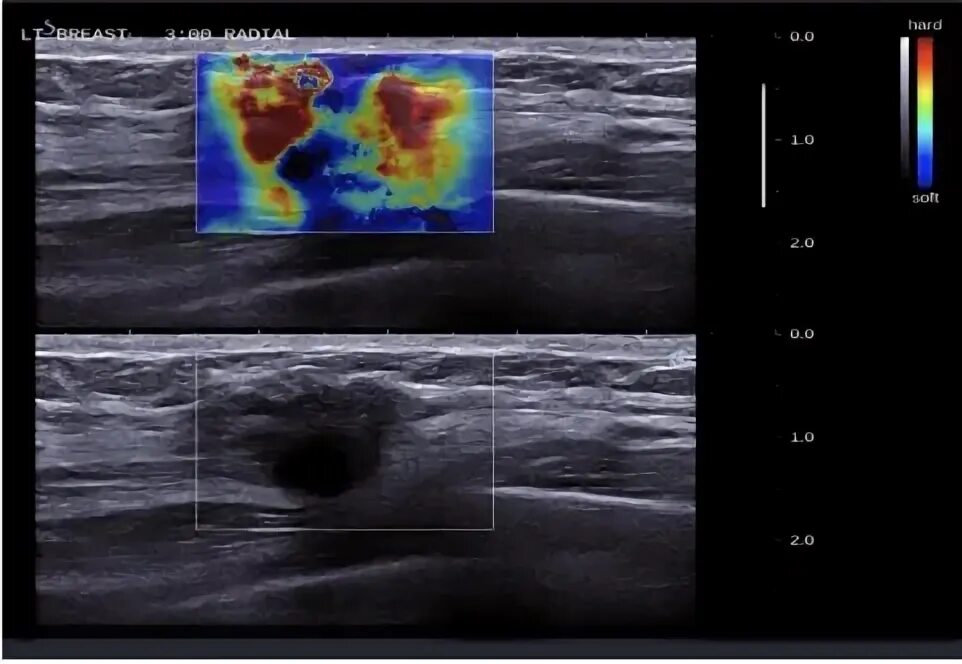

Эластометрия подготовка к процедуре